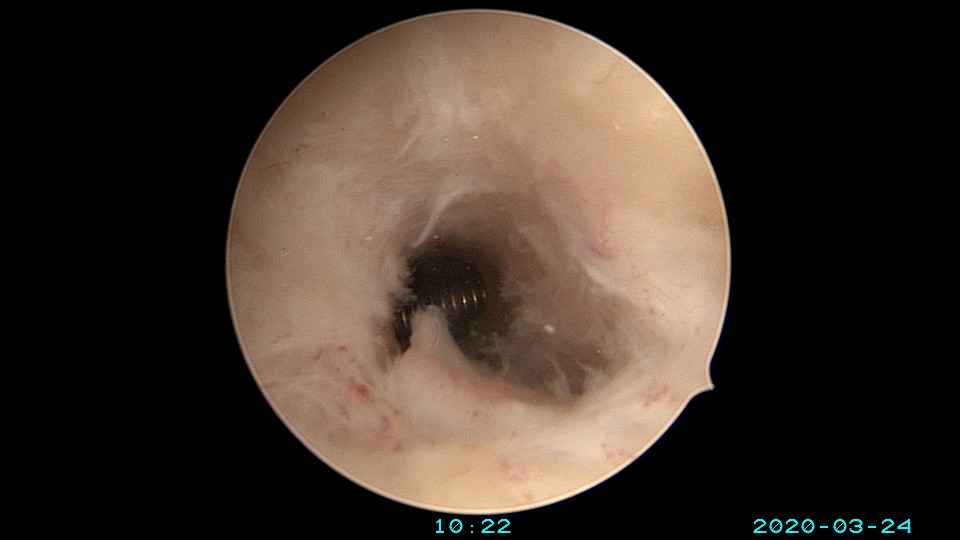

患者65岁,G1P1,顺产1次。安环30年,绝经10年。外阴白斑,阴道明显萎缩,无法置入扩阴器,阴道内镜方式找到宫颈外口,宫颈萎缩,穹隆几乎消失,无法夹持宫颈,宫颈管见多个息肉,宫颈内口狭窄坚硬,难以扩张。微型异物钳探查宫腔方向,用异物钳、微型剪刀扩大宫颈内口失败,改用双极电针切开宫颈内口,但镜子仍无法进入宫腔。用异物钳反复牵拉O型环至阴道内,中弯钳配合卵圆钳拉出节育环,环变形。有人问我何不用取环钩取环,这个病人探针和取环钩都无法发挥作用。